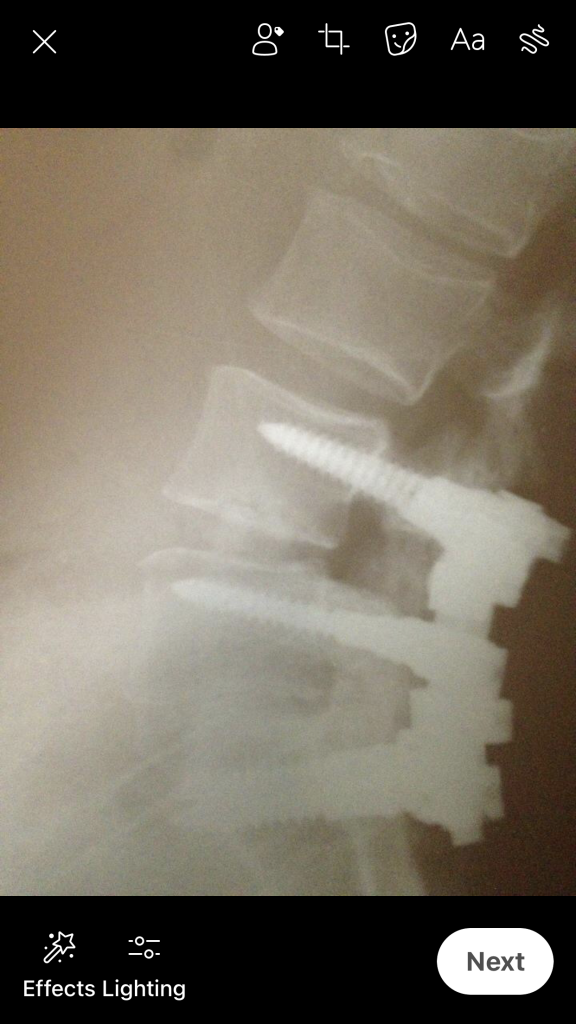

When I was 32, I was suffering from degenerative disc disease (DDD) and was a candidate for a double fusion. I searched for the best doctor in the US and found Dr. Frank Cammisa at HSS. He was extremely professional and knowledgeable! My fusion was expected to last 10 years, and I am on year 19. I highly recommend him for an advanced spine problem. His work is perfectionism at its finest! His talent let me raise my children almost pain-free along with enjoying many hobbies such as cycling! I was also able to conceive and have a beautiful healthy baby after my fusion!